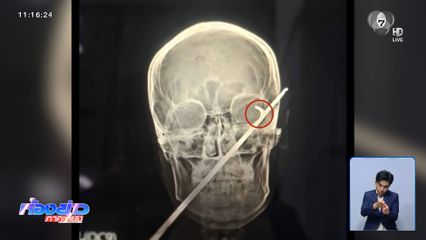

นี่เป็นฟิล์มเอกซเรย์ศีรษะของ นายวิชาบูรณ์ ขวัญปาก อายุ 27 ปี ชาวจังหวัดบุรีรัมย์ หลังเข้ารับการรักษาตัวที่โรงพยาบาลศูนย์บุรีรัมย์ เพราะถูกลูกดอกเหล็กยาวกว่า 60 เซนติเมตร แทงเข้าเบ้าตาซ้ายทะลุถึงสมอง ถ้าไม่ติดแง่งเล็ก ๆ ที่อยู่ตรงเบ้าตา มีโอกาสที่จะทะลุศีรษะได้เหมือนกัน ซึ่งเหตุการณ์นี้เกิดขึ้นระหว่างที่ นายวิชาบูรณ์ ออกไปยิงกบ แต่ลูกดอกกลับย้อนกลับมาแทงเบ้าตา และยังกัดฟันขี่รถจักรยานยนต์มาขอความช่วยเหลือที่บ้าน

ล่าสุด แพทย์ผ่าตัดเอาลูกดอกออกมาแล้ว แต่ยืนยันว่าไม่ได้ทะลุถึงสมองตามที่กังวลในตอนเเรก ที่น่ากังวล คือ อาการเบ้าตาซ้าย จะกลับมาใช้งานได้หรือไม่